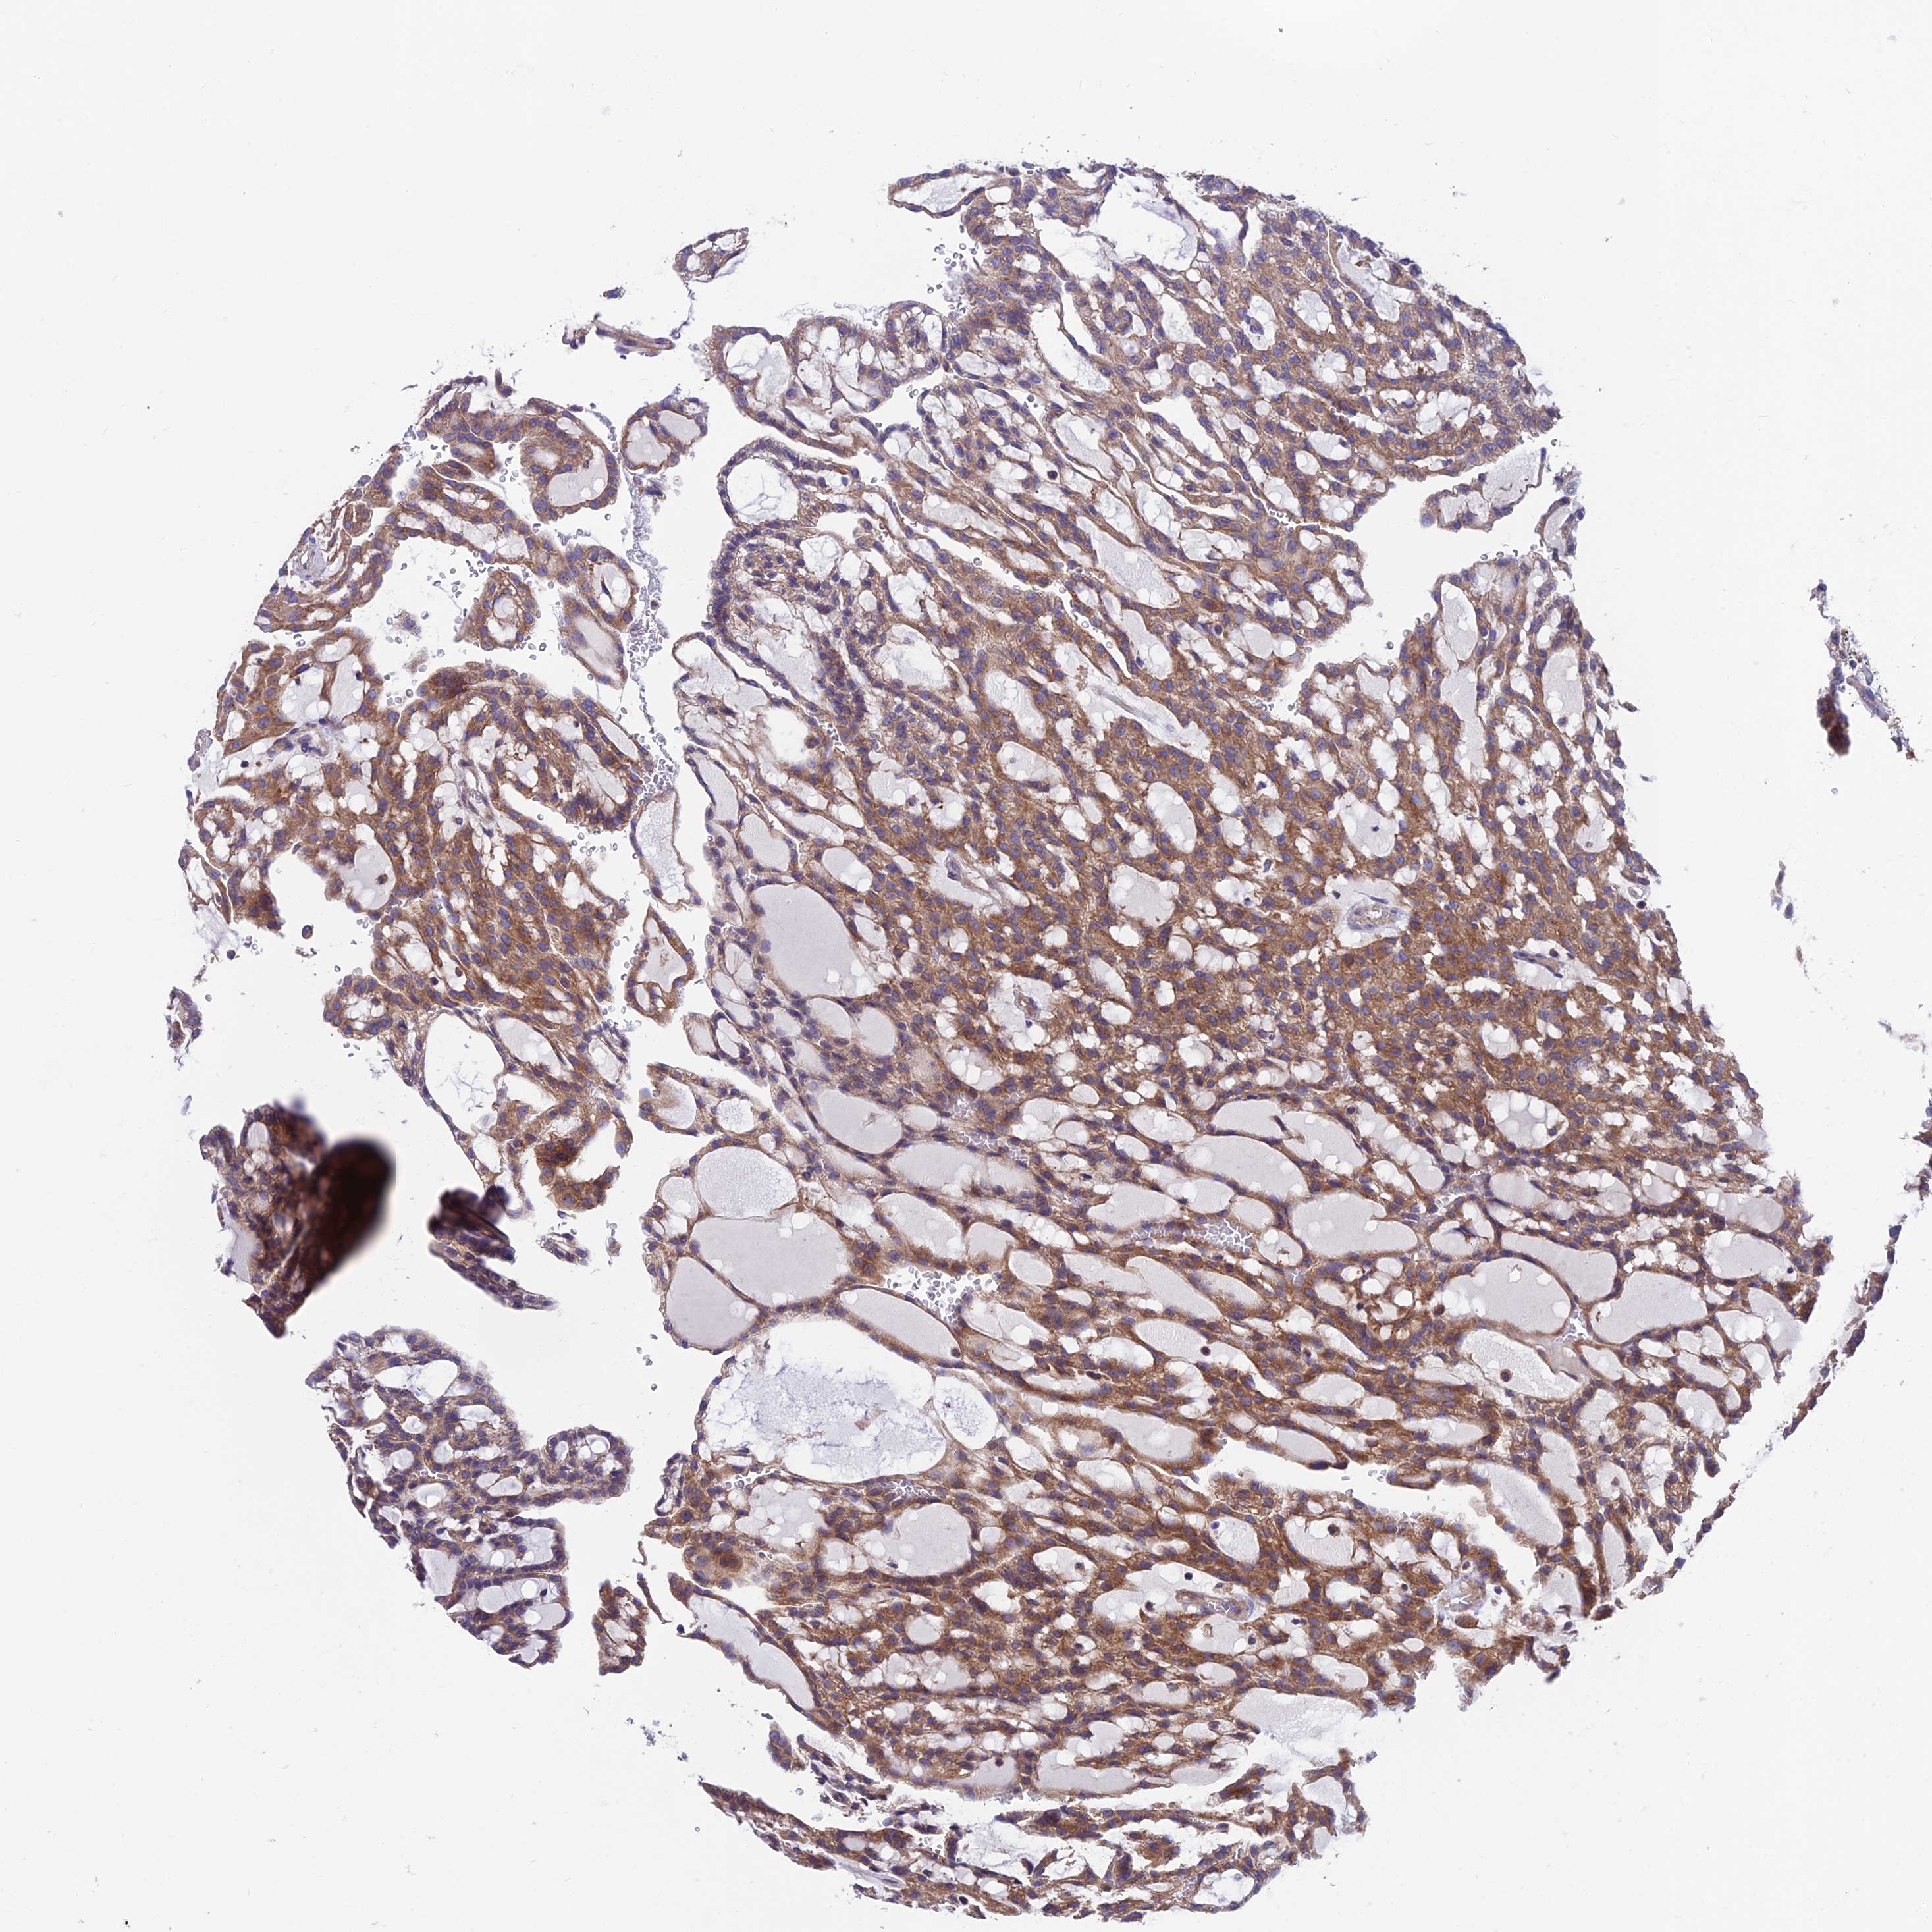

KIDNEY RENAL PAPILLARY CELL CARCINOMA (TCGA) - Interactive survival scatter ploti

The Survival Scatter plot shows the clinical status (i.e. dead or alive) for all individuals in the patient cohort, based on the same data that underlies the corresponding Kaplan-Meier plots. Patients that are alive at last time for follow-up are shown in blue and patients who have died during the study are shown in red.

The x-axis shows the expression levels (FPKM) of the investigated gene in the tumor tissue at the time of diagnosis. The y-axis shows the follow-up time after diagnosis (years). Both axes are complimented with kernel density curves demonstrating the data density over the axes. The top density plot shows the expression levels (FPKM) distribution among dead (red) and alive patients (blue). The right density plot shows the data density of the survived years of dead patients with high and low expression levels respectively, stratified using the cutoff indicated by the vertical dashed line through the Survival Scatter plot. This cutoff is automatically defined based on the FPKM cutoff that minimizes the p-score. The cutoff can be changed by dragging the vertical line or by entering a cutoff value in the square labeled "Current cut-off".

Under the Survival Scatter plot the p-score landscape (black curve; left axis) is shown together with dead median separation (red curve; right axis). Dead median separation is the difference in median mRNA expression between patients who have died with high and low expression, respectively. It is calculated as follows: median FPKM expression of dead patients with high expression - median FPKM expression of dead patients with low expression. This is intended to aid the user in visually exploring custom cutoffs and the associated p-scores and dead median separation.

Individual patient data is displayed and can be filtered by clicking on one or more of the category buttons on the top of the page. Categories describing expression level and patient information include: high, low, alive, dead, female, male and tumor stages. The scale of the x-axis can be toggled between linear and log-scale by clicking on the "x log" button. Mouse-over function shows TCGA ID, patient information and mRNA expression (FPKM) for each patient.

& Survival analysisi

Kaplan-Meier plots summarize results from analysis of correlation between mRNA expression level and patient survival. Patients were divided based on level of expression into one of the two groups "low" (under cut off) or "high" (over cut off). X-axis shows time for survival (years) and y-axis shows the probability of survival, where 1.0 corresponds to 100 percent.

VPS16 is not prognostic in Kidney Renal Papillary Cell Carcinoma (TCGA)

Best expression cut offi

Based on the FPKM value of each gene, patients were classified into two groups and association between prognosis (survival) and gene expression (FPKM) was examined. The best expression cut-off refers the FPKM value that yields maximal difference with regard to survival between the two groups at the lowest log-rank P-value. Best expression cut-off was selected based on survival analysis .